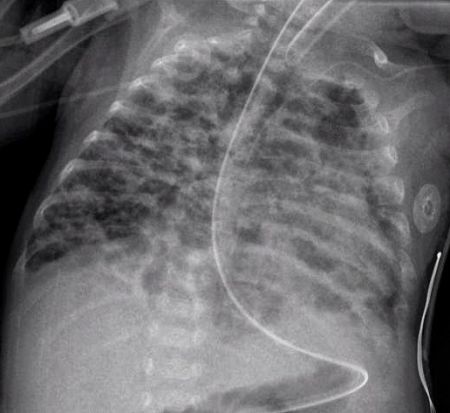

- CXR shows with hyperinflation, low diaphragm, atelectasis, cystic changes.

- Chest radiograph with diffuse abnormal findings characteristic of bronchopulmonary dysplasia.